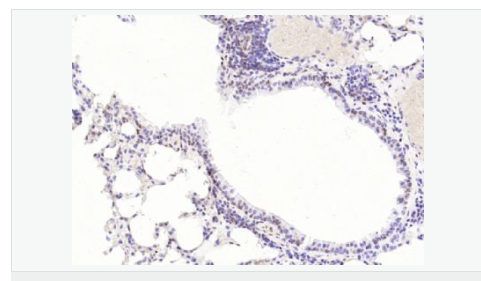

image.png